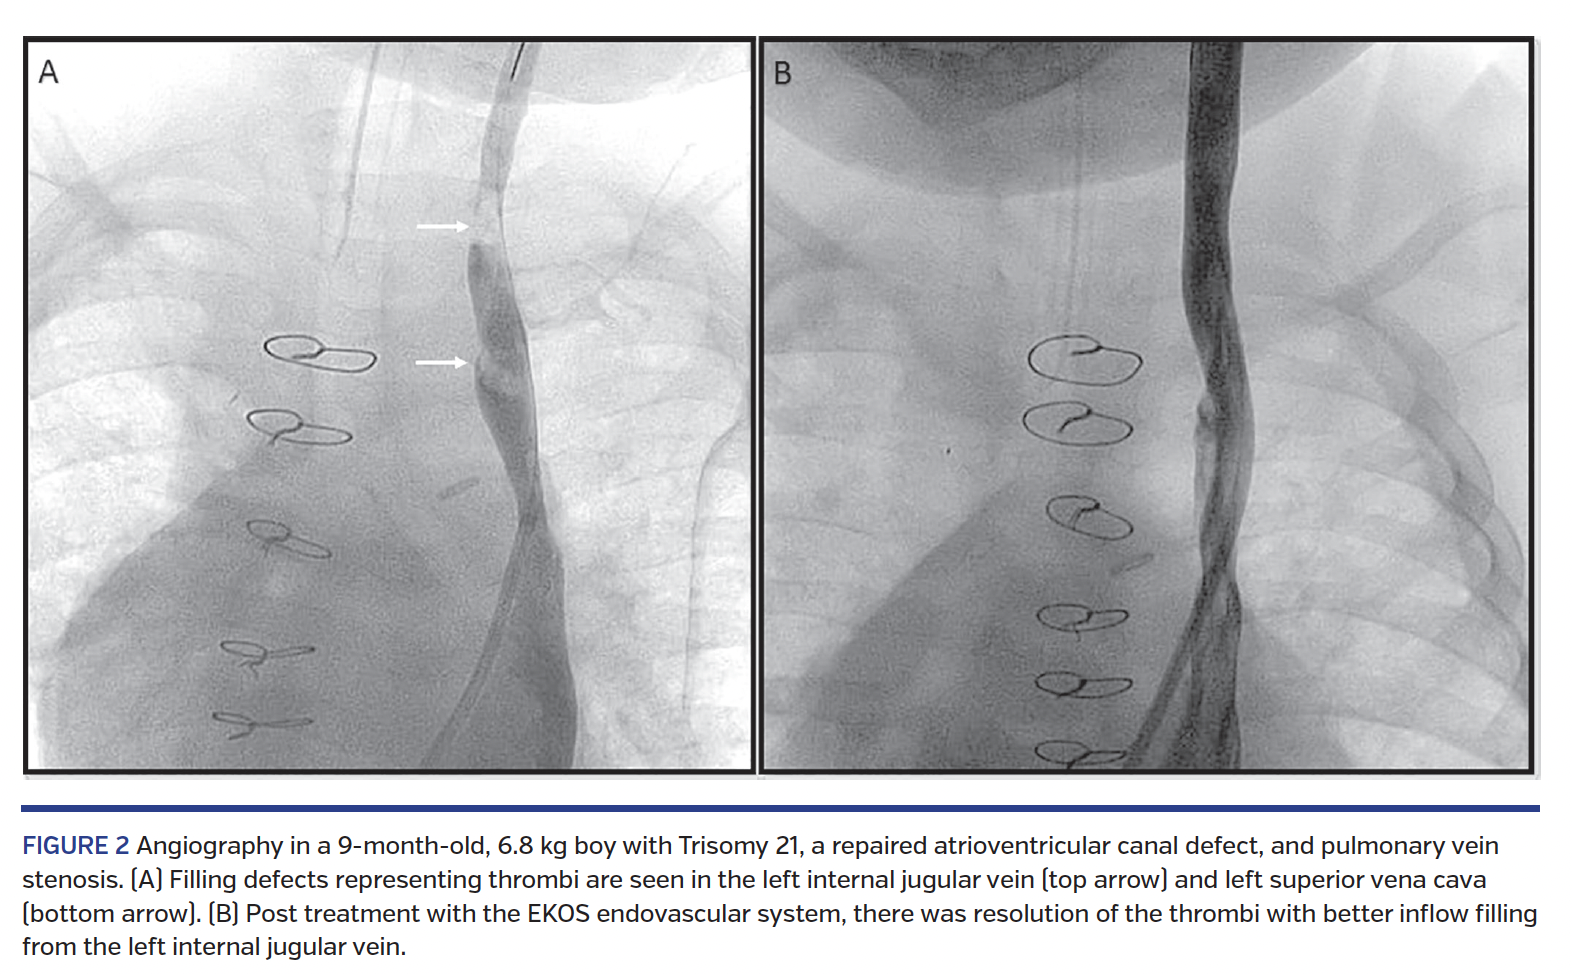

Immediate results. Therapy was not completed in 1 patient (described above). Significant improvement in clot burden/symptoms was seen in 8 patients (no improvement seen in 1 patient with acute and chronic arterial thrombosis). Angiographic/CT-based improvement on follow-up imaging was seen in 7 of the 8 patients who underwent successful therapy (Figures 1 and 2). One patient post Fontan palliation with bilateral pulmonary embolism did not receive follow-up imaging due to immediate postpartum status, but had significant symptomatic improvement following 12 hours of therapy.

Targeted thrombolytic therapy with the EKOS endovascular system was performed in 20 vessels in 10 patients (Table 1). There were 3 adult patients, 2 with congenital heart disease and 1 with short-gut syndrome who was cared for at our institution since infancy due to venous occlusions. The median age was 11.2 years (range, 9 months to 34.2 years) and median weight was 46.6 kg (range, 6.8-101.6 kg). Risk factors for thromboses and presenting features can be seen in Table 1.